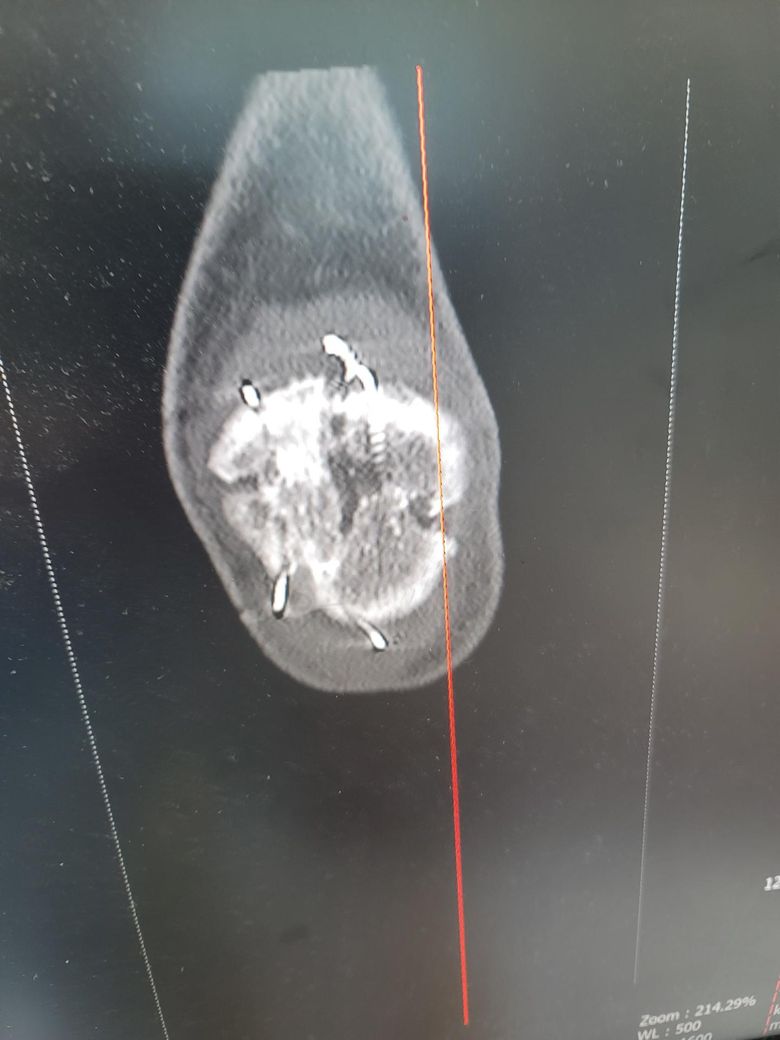

슬개골수술후 5개월차 ct입니다 분쇄골절 7조각이여도 엑스레이상 잘붙은즐알았는데 ct를찍어봤더니 양쪽 끝부분이 덜붙었더라구요 혹시 안붙으면 재수술하거나 뼈이식을 다시해야되나요? 걷거나 큰 통증은없는데

안붙을까봐 걱정입니다

• 1번 째 사진

• 2번 째 사진